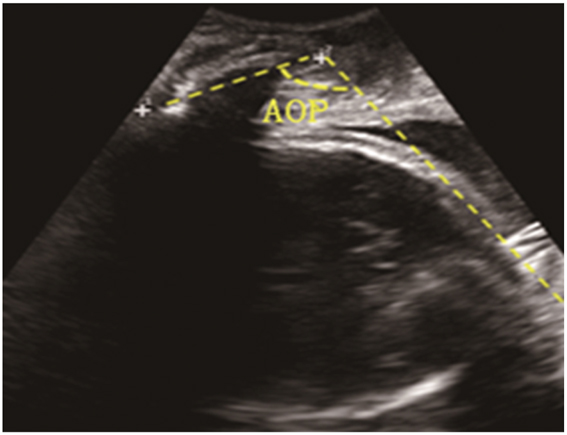

The standard AOP measurement should display the binary structure of the pubic symphysis with the maximum diameter and the lowest point of the skull cortex in the same section (Figure 2) [10], [11], [12]. Participants were encouraged to empty their bladder before measurement, and excessive residual urine detected by ultrasound would be catheterized if necessary. Ultrasound probe was placed at the pubic symphysis and pressed tightly against the vaginal opening at a longitudinal angle to obtain a standard section. A midsagittal image was obtained at the uterine contractions. Each patient was measured three times to take the average value. All the measurements were performed by two senior physicians, and images did not meet the standard were discarded.

Figure 2:

The standard image of angle of progression.

In addition to rotation, the descent of the fetal head is also an important factor determining the birth process, and AOP is a good ultrasound indicator that reflects the descent of the fetal head currently [10], [13], [14], [15]. Therefore, when measuring the fetal orientation, AOP values were obtained at the same time point and we attempted to describe the relationship between the fetal orientation and AOP. When the AOP value was 95–109°, only 26.1 % women were in the occipital anterior position. When the AOP value was ≥125°, 66.7 % women were in the occipital anterior position. These results fully demonstrated that the progression of the labor process was a continuous process with synchronous descent and rotation of the fetal head.